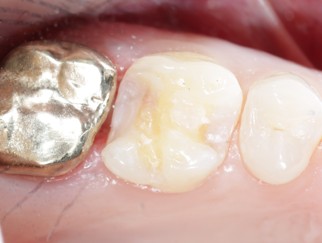

Extensive training and experience give prosthodontists a unique understanding of restoring the dynamics of a smile and healthy mouth with the creation of tooth prostheses. Becoming a prosthodontist requires an additional three years of specialty training after obtaining a DMD (Doctor of Dental Medicine) or DDS (Doctor of Dental Surgery) degree.